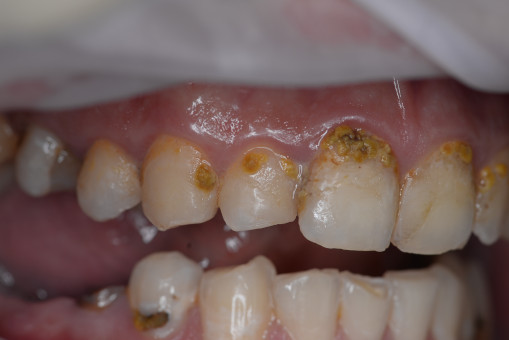

А прежде, чем вы посмотрите фотографии «до» и «после» лечения слизистой оболочки полости рта, проведенных в нашей клинике, хочу поблагодарить большое количество наших пациентов, которые поверили, прониклись нашей концепцией, и мы вместе, именно вместе победили болезни десны, гингивит и пародонтит!

До/после лечения